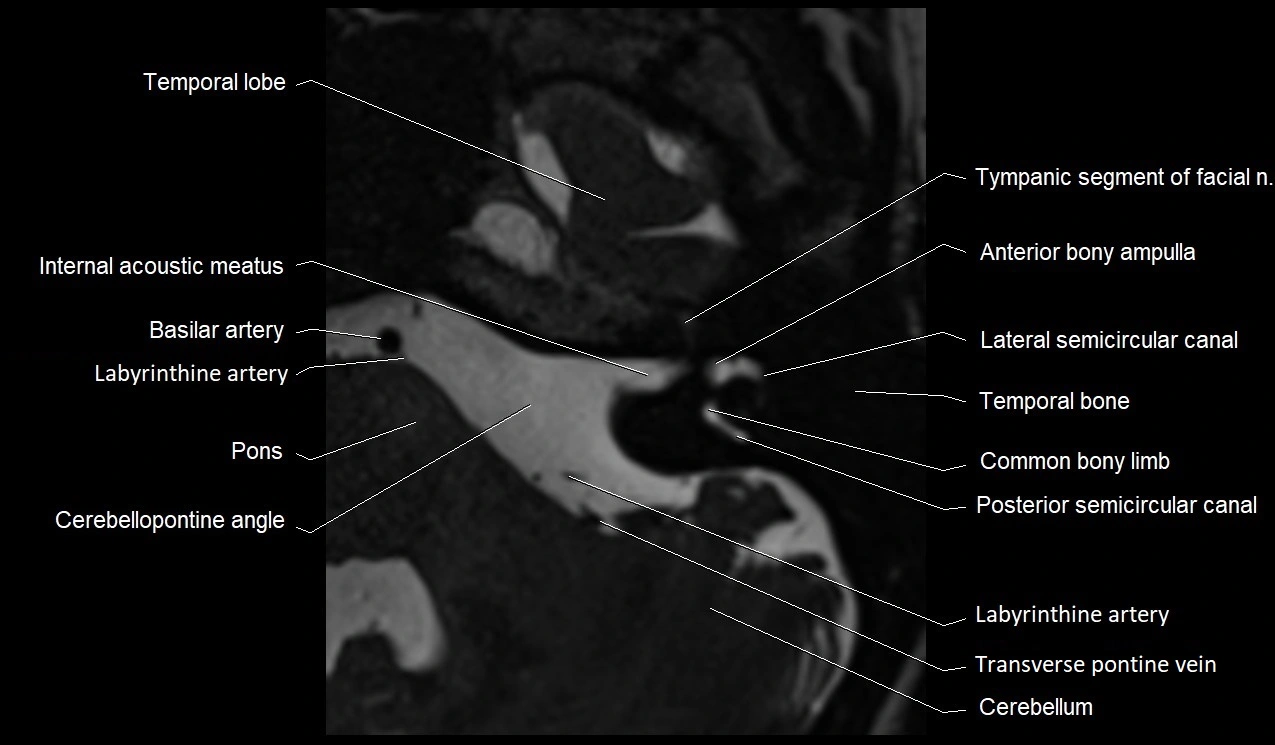

MRI Appearance

• The abducens nerve is a small, thin, linear structure

• Best visualized on high-resolution T2-weighted 3D MRI sequences (e.g., FIESTA or CISS)

• Seen as a hypointense (dark) line running from the brainstem at the pontomedullary junction, traversing the prepontine cistern, and entering Dorello’s canal under the petrosphenoidal ligament, then into the cavernous sinus, and finally the orbit

• May be challenging to visualize in standard MRI due to its small size

• Pathology may be inferred by absence, displacement, or enhancement of the nerve